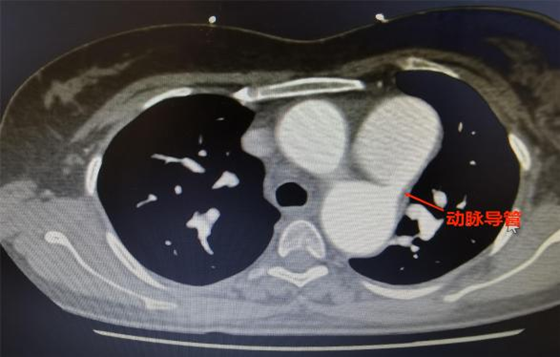

湘雅常德医院心胸外科何志伟医师接诊患者后,完善相关检查发现:患者存在先天性的动脉动脉未闭,即新生儿出生后主动脉与肺动脉之间的交通并没有完全闭锁,还存在一个约7mm左右的通道。主动脉有血液分流至肺动脉,导致肺动脉高压以及左心长期高负荷工作,左心扩大,长此以往易导致患者心功能衰竭。

9月15日,在心胸外科和麻醉科的共同配合下,我院首例胸腔镜下动脉导管未闭结扎术顺利开展,手术前麻醉科医生经过食道超声确定患者动脉导管未闭存在大量分流。术中,心胸外科医生在食道超声引导下确定动脉导管未闭的位置并充分游离导管周围组织,导管游离后以丝线反复结扎3次并最后以钛夹加固夹闭确保结扎确切。最后在术中食道超声检查下确定患者动脉导管未闭结扎完全,分流消失,手术顺利完成。患者术后恢复良好,第二天便能下床活动,听诊心脏杂音完全消失。